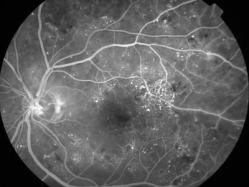

rétinopathie diabétique pré-proliférante

IM000023.jpg